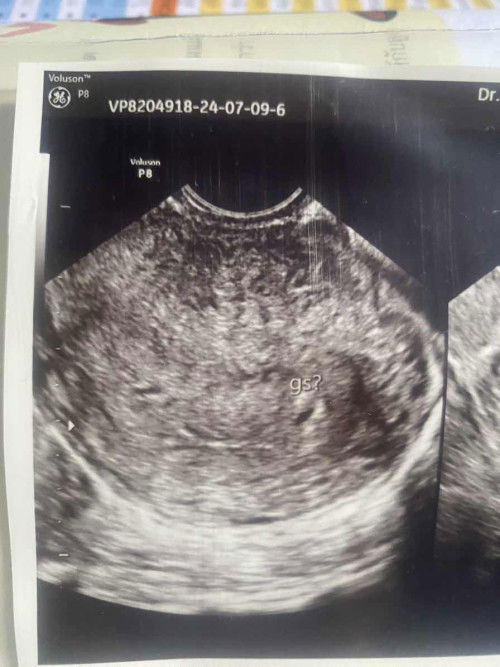

แม่ๆคนไหนเคยเจอเคสถุงตั้งครรภ์ไม่สวยบ้างคะ

#ท้องแรกคะ คุณหมอแจ้งว่า ถุงตั้งครรภ์ไม่ค่อยสวยเท่าไหร่ เสี่ยงแท้งค่ะ ช่วงนี้ก็ไม่ควร เดินหรือยืนเยอะ แม่ๆคนไหนเคยมีประสบการ์ณแบบนี้บ้างคะ